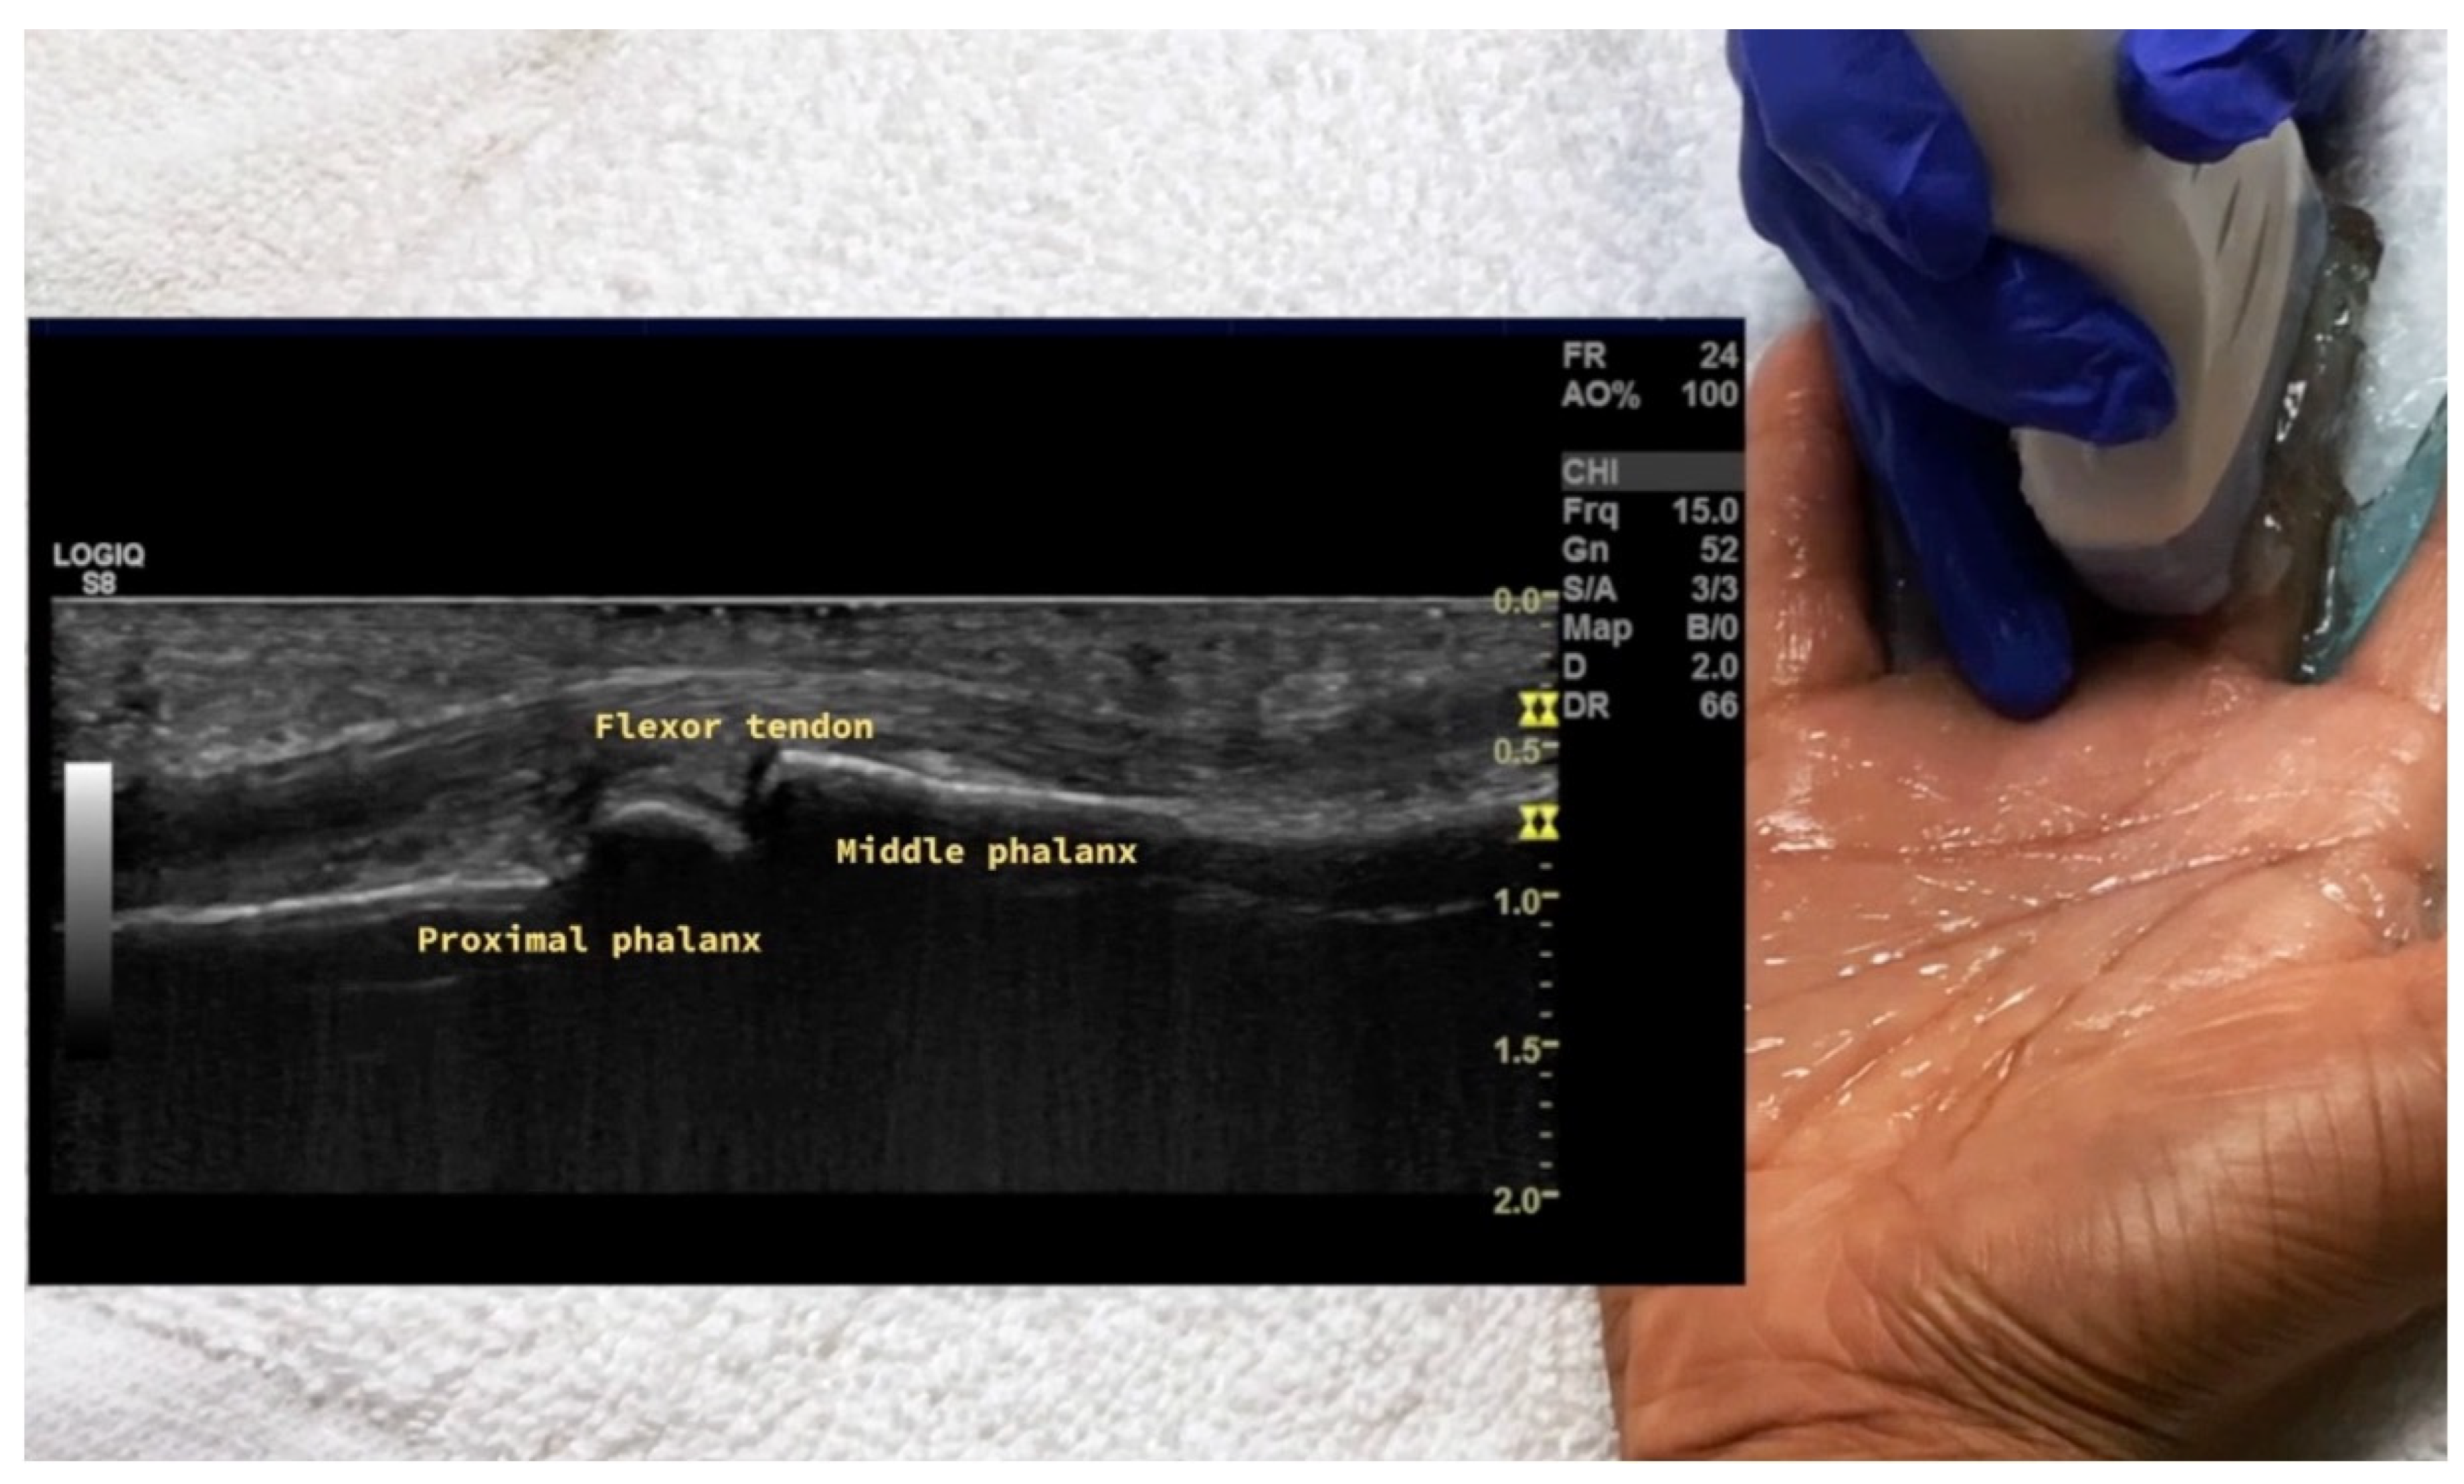

4.1.2. Volar Aspect

2.2. Tendon Pathology

2.2.1. Tenosynovitis

- Hughes, M.; Manning, J.; Moore, T.; Herrick, A.L.; Chitale, S. Ultrasound findings in finger flexor tendons in systemic sclerosis: A cross-sectional pilot study. J. Scleroderma Relat. Disord. 2020, 5, 77–82. [Google Scholar] [CrossRef]